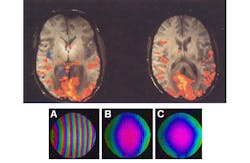

Multislice acquisition of 2D MR images usually processes one slice at a time. Scanning multiple slices at one time can accelerate the process, but this requires a more precise excitation process. This multislice excitation uses RF pulses with distinct phase tagging of each slice, which required a method to disentangle the information from overlapping slices. A Pentek Model 78621 dual-channel 800-MHz digital-to-analog converter (DAC) was used in the interpolating mode to create RF pulses with a 2-ns sampling rate and smooth stair-step-less modulation.

The synthesized RF pulses provide a coherent image (see the figure) compared to the first, conventionally obtained image. The scans were performed in conjunction with a GE Signa EXCITE 3 T MR Scanner. The accuracy of the DAC board provided a reference signal that compensated for the phase of off-resonance frequencies used to excite different slices.